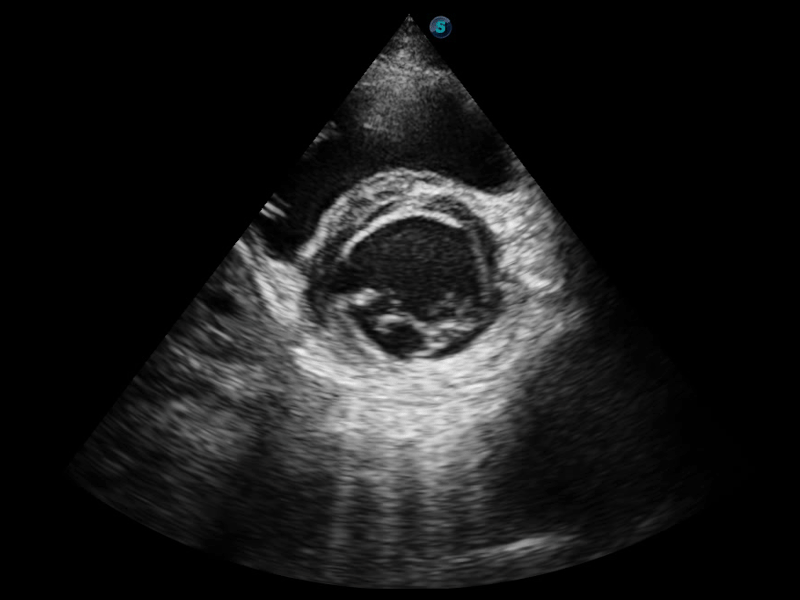

临床图像

组织多普勒

组织多普勒成像功能,可提供心肌运动速度和其他临床信息,使临床医生能够分析和比较患者心脏不同部位的运动。